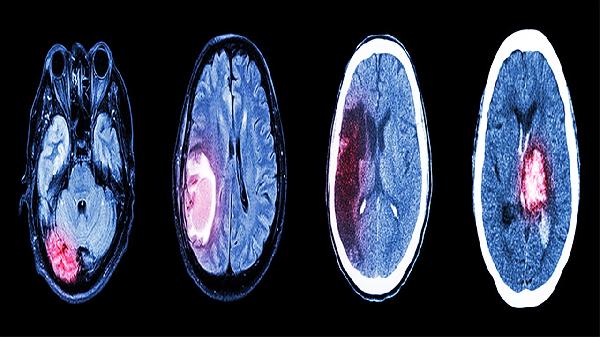

三、中风后遗症

部分中风后遗症患者在康复期使用益智康脑丸,有助于改善语言不利、肢体麻木等症状。中风后遗症可能与脑血栓形成、脑出血等因素有关,通常表现为偏瘫、吞咽困难等症状。临床常配合血栓通胶囊、长春西汀片等药物治疗。